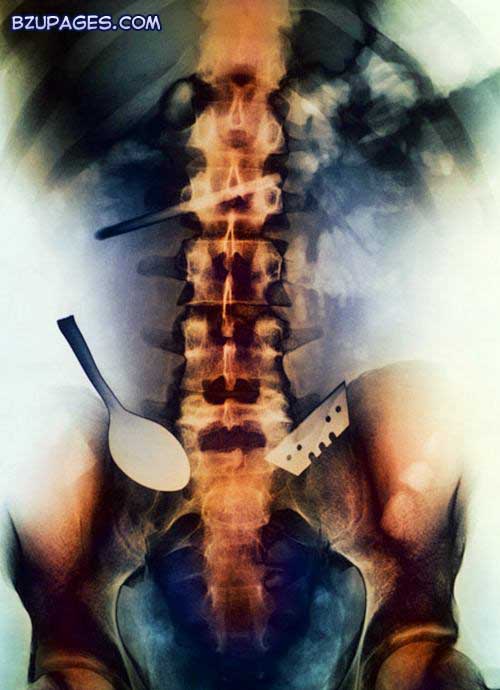

Attachment 21982

A coloured X-ray of objects swallowed and lodged in the intestine of a patient, including a spoon and a blade.